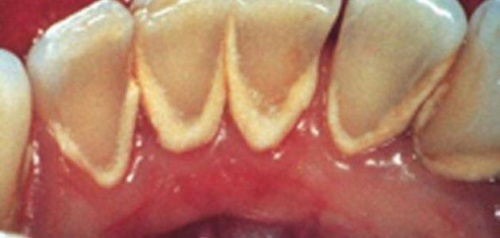

افتراضي كيف أتخلص من طبقة الترسبات على أسناني ؟

الجير هو طبقة من الترسبات يتعرض لها جميع أنواع الأسنان، مما يؤدي إلى خشونة سطح الأسنان و تغير لونها، كما يمكن أن يؤدي تجمع الجير على الأسنان إلى تسوسها أو الإصابة بأمراض اللثة، إن العناية اليومية بالأسنان تمنع تشكل هذه الطبقة، و بالتالي فإن هذه الخطوة تعتبر الأولى نحو تنظيف الاسنان من الجير.

تنظيف الأسنان من الجير

لكن على كل حال يمكن إزالة هذه الطبقة و منع تشكلها، و يمكن تنظيف الأسنان بأكثر من طريقة و في ما يلي أبرز هذه الطرق.